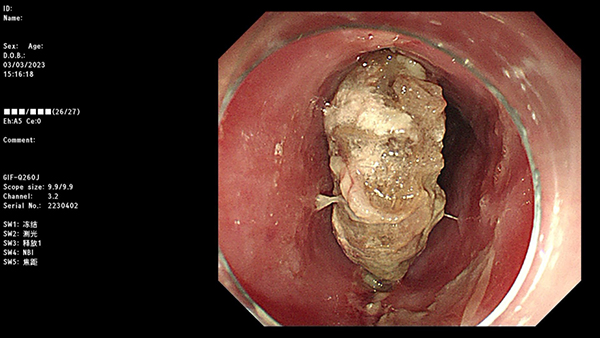

内镜下食管异物图

当机立断,何主任找到患者家属说:“异物必须取出,但是风险极高,有可能目前已经出现食管穿孔,而倘若异物扎入主动脉弓,取出异物则导致消化道出血,可能危及生命,因此我们需要做好随时开胸手术的准备。”

手术开始,所有人的心情都非常紧张,唯恐鲜血喷涌而出。幸运的是,何主任用异物钳夹住异物一端后使异物与食管呈一斜面,然后缓慢取出另一端,两端并无较多出血。但镜下仔细观察创面后发现,创面较深且随呼吸上下浮动。“穿孔了!快拿三臂夹。”何玉琦主任立马做出准确判断,所有人的心也都提到嗓子眼儿。